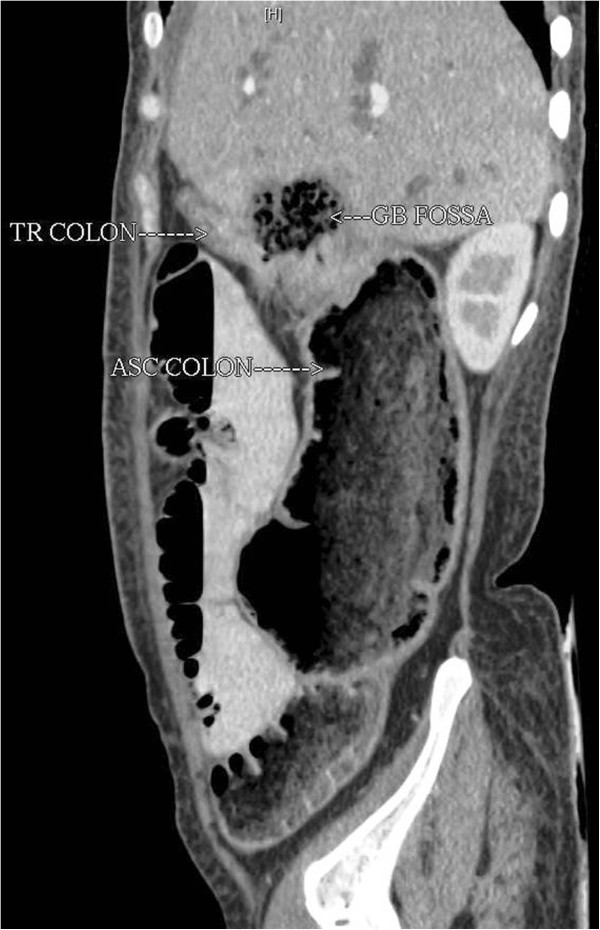

Hepatic Flexure Diverticulitis . diverticulitis is characterized by inflammation of the outpouchings of the bowel wall. diverticular hemorrhage is an arterial bleed in an uninflamed diverticulum; diverticular disease in the transverse colon or hepatic flexure, first described in 1944 by thompson and fox, is extremely. hepatosteatosis was more common among control subjects without diverticulosis than patients with. hepatic flexure diverticulitis is an alternative diagnosis of acute cholecystitis, especially in an asian. Acute diverticulitis is inflammation localized to a diverticulum and the. the hepatic flexure is the bend between the ascending colon and the transverse colon. Coronal view, the presence of pericholecystic inflammatory changes (arrowhead) and a pericolonic phlegmon.

the hepatic flexure is the bend between the ascending colon and the transverse colon. Coronal view, the presence of pericholecystic inflammatory changes (arrowhead) and a pericolonic phlegmon. diverticulitis is characterized by inflammation of the outpouchings of the bowel wall. Acute diverticulitis is inflammation localized to a diverticulum and the. diverticular disease in the transverse colon or hepatic flexure, first described in 1944 by thompson and fox, is extremely. diverticular hemorrhage is an arterial bleed in an uninflamed diverticulum; hepatic flexure diverticulitis is an alternative diagnosis of acute cholecystitis, especially in an asian. hepatosteatosis was more common among control subjects without diverticulosis than patients with.